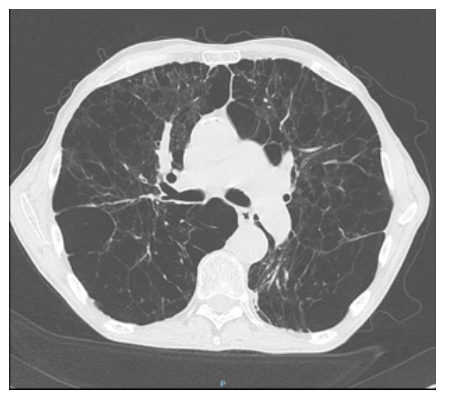

La radiographie de thorax est la suivante.

Figure 1.

Tableau radiologique pulmonaire typique d’une bronchopneumopathie chronique obstructive (BPCO) avec distension thoracique et emphysème. Le piège dans lequel il ne faut pas tomber est de penser à un syndrome interstitiel devant la présence de « traits » diffus faisant croire à des réticulations. Ces traits correspondent en fait aux structures bronchiques et vasculaires, toutes en direction du hile à la différence des réticulations du syndrome interstitiel qui seraient alors orientées dans toutes les directions, dessinant ainsi des polygones correspondant aux lobules pulmonaires. Ces structures bronchovasculaires paraissent très visibles par contraste (raréfaction de la trame microvasculaire environnante liée l’emphysème) et par la présence très probable d’une hypertension pulmonaire (dilatation des artères pulmonaires et de leurs branches).